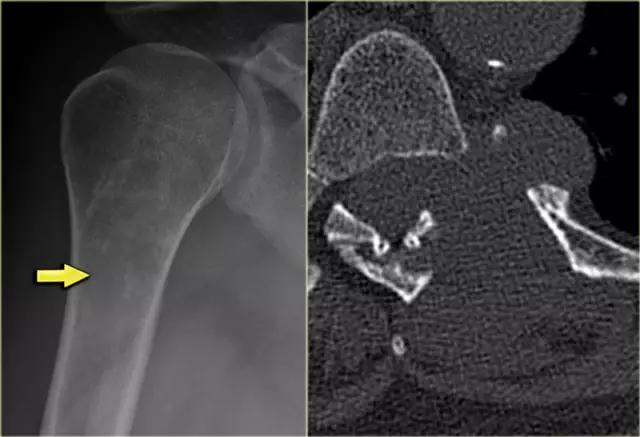

上图是一个有分叶的部分边界不清楚的肱骨近端的溶解性病变。钙化的存在表明这是一个软骨形成的肿瘤。具有皮质受累和扩张的溶解部分应该高度怀疑高级软骨肉瘤。